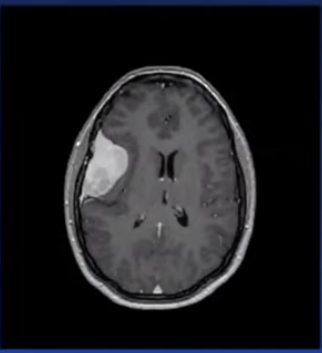

Q185. A 35-year-old male presents with a complaint of recurrent headaches. On further investigation, the following MRI was received. What is the most likely diagnosis?

- Meningioma

- Glioma

- Medulloblastoma

- Pilocystic astrocytoma

Answer: A